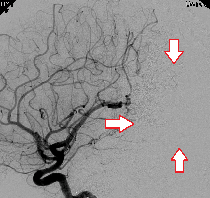

もやもや病

頭蓋内血管の閉塞がみられます。血管造影では血管が閉塞し、周囲に「もやもや病」がみられます。

バイパス手術によって血管が頭蓋骨を通り、皮膚の太い血管と脳をつなげて治療します。

もやもや病のMRA画像

血管造影検査の画像

バイパス術後のCTA画像